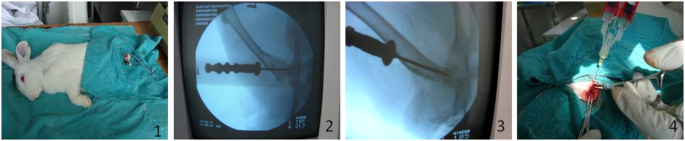

No postoperative infection or death was observed in all 48 white rabbits. After core decompression surgery, C-arm fluoroscopy could accurately reach the necrotic area of the femoral head, and BMSCs combined with bioprotein glue successfully reached the femoral head area (Fig. 1).

Accurate implantation of biological proteins with BMSCs in the femoral head area.